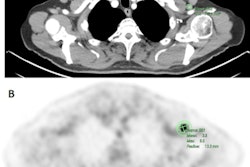

Both single and dual-tracer PET/CT were tolerated well by all patients, without any recorded adverse reactions or side effects, and all primary tumors could be clearly detected on both scans. However, in one patient, F-18 FDG revealed metastasis in only one mediastinal lymph node, whereas dual-tracer accumulation revealed two additional lymph nodes of the same drainage region.

One mediastinal lymph node of another patient showed discrete nonsuspicious F-18 FDG tracer accumulation, but suspiciously high dual-tracer accumulation. In addition, dual-tracer PET/CT displayed a higher number of liver metastases than F-18 FDG-PET/CT alone in a patient with a metastasis in the adrenal gland.

(A) Single-tracer PET/CT with F-18 FDG showing fused images in the axial plane of a primary tumor at the gastroesophageal junction with a metastasis in the left adrenal gland and liver metastases. (B) Maximum intensity projection (MIP) of single-tracer PET images displaying high uptake in brain tissue, tracer accumulation around the injection side at the right elbow, lymph node metastasis in the left upper mediastinum, multiple abdominal lymph node metastases, and liver metastases. An additional benign accumulation of FDG is visible, caused by right-sided thoracolumbar osteoarthritis. (C) Transverse section of fused dual-tracer F-18 FDG and Ga-68 FAPI-46 PET/CT of the same patient. (D) As all images were visually normalized to the uptake of the liver, MIP of dual-tracer PET/CT in the same patient shows a less pronounced tracer accumulation in the brain tissue, compared to single-tracer PET/CT. In addition to lesions detected with single-tracer PET/CT, further abdominal lymph node metastasis and liver metastases are visualized via dual-tracer PET/CT. The focal tracer accumulation in the right vein angle is due to intravenous tracer accumulation from the former tracer depot at the right elbow. Image courtesy of the Journal of Nuclear Medicine.Since the diagnostic performance of Ga-68 FAPI-46-PET/CT is best shortly after injection and F-18 FDG-PET/CT is currently the gold standard, the authors so far recommend the injection of Ga-68 FAPI-46 as a second tracer after the F-18 FDG-PET/CT scan.